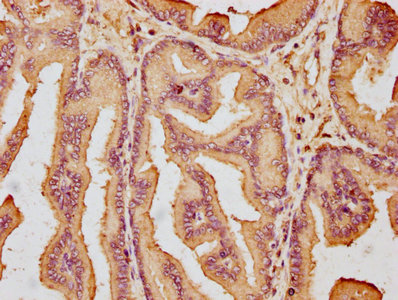

IHC image of CSB-PA880974LA01HU diluted at 1:600 and staining in paraffin-embedded human prostate tissue performed on a Leica BondTM system. After dewaxing and hydration, antigen retrieval was mediated by high pressure in a citrate buffer (pH 6.0). Section was blocked with 10% normal goat serum 30min at RT. Then primary antibody (1% BSA) was incubated at 4°C overnight. The primary is detected by a biotinylated secondary antibody and visualized using an HRP conjugated SP system.